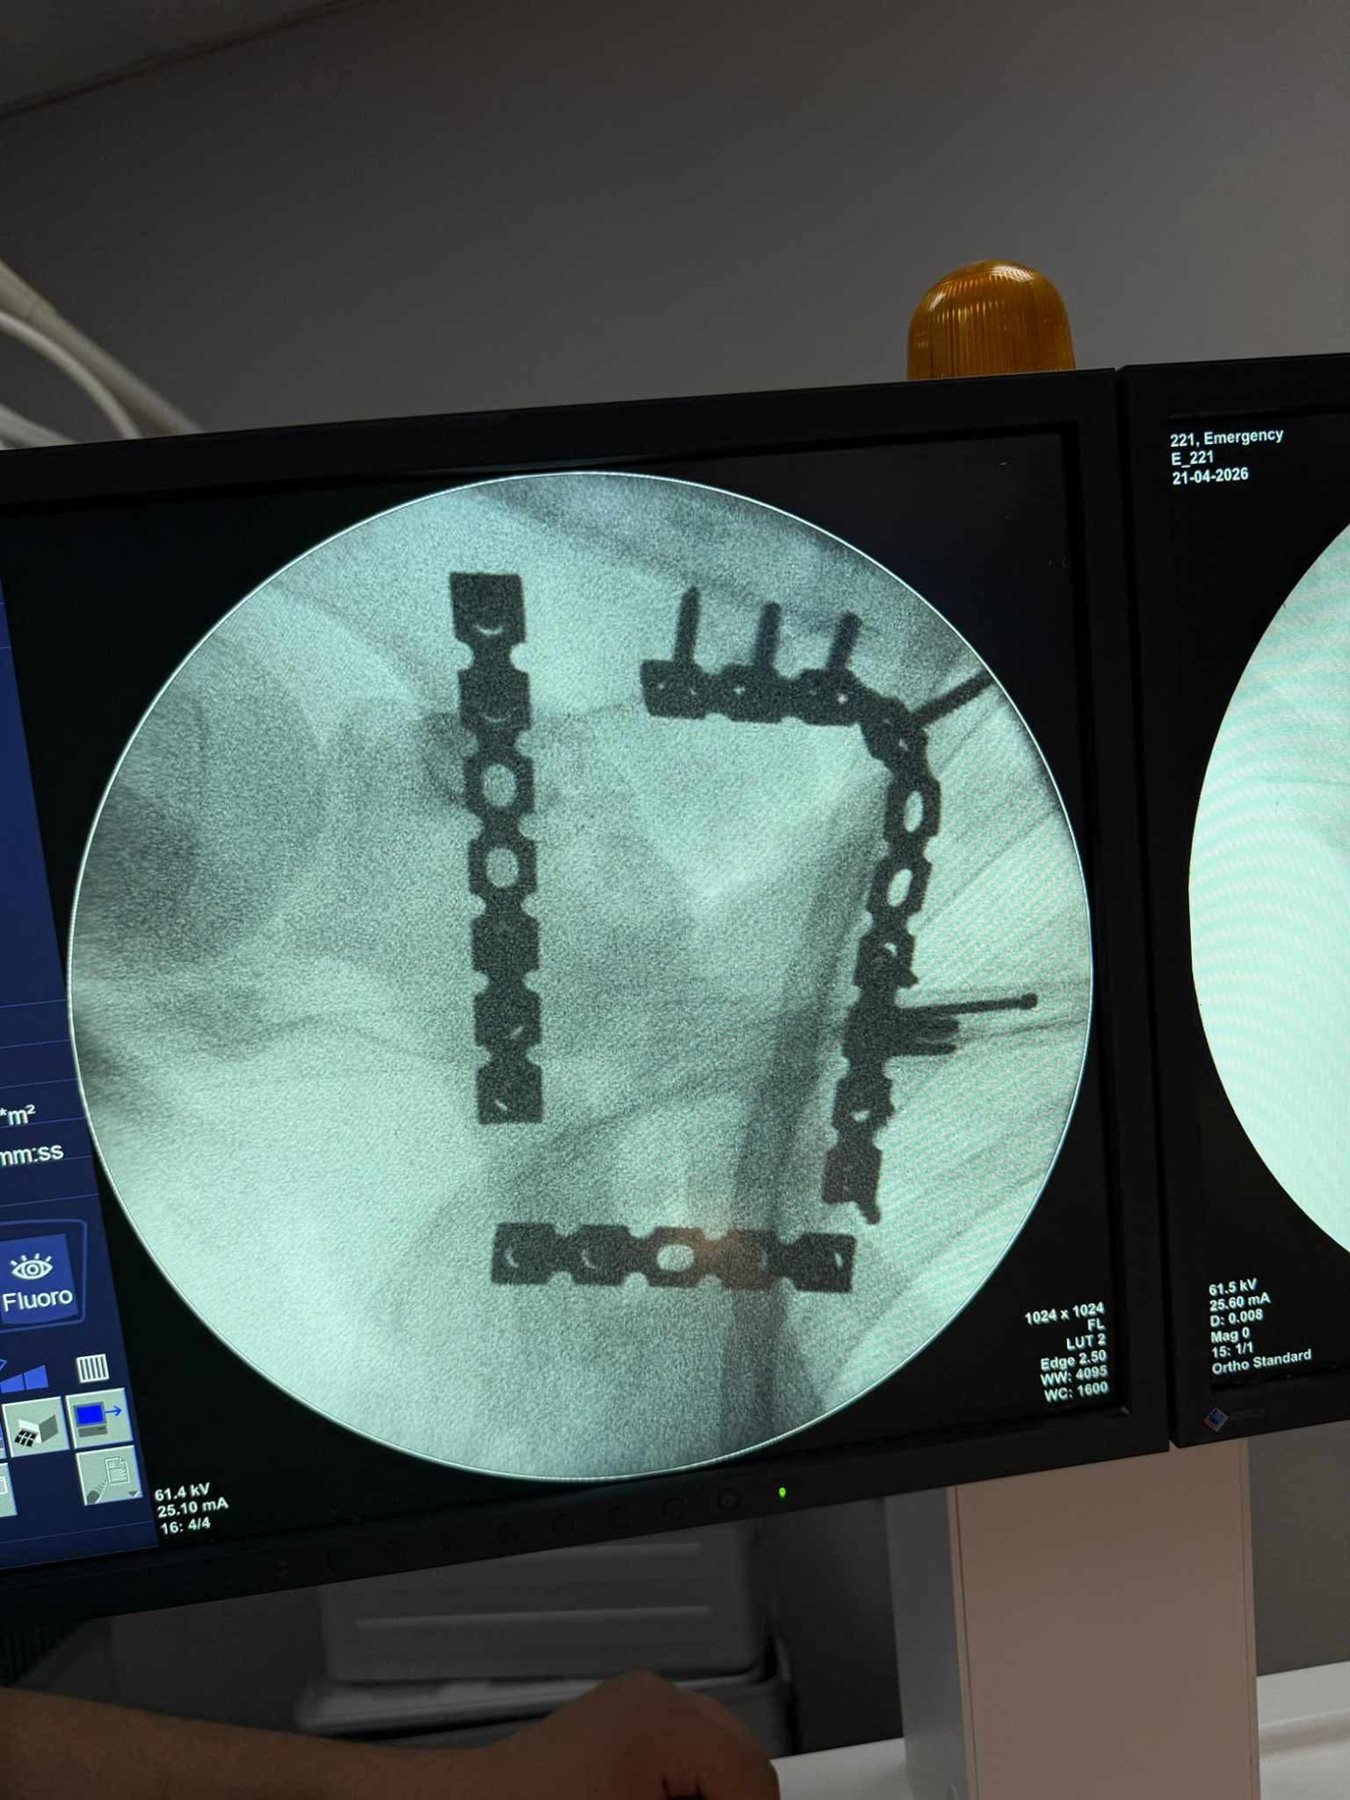

خضع المريض لعملية جراحية معقدة استمرت نحو 4 ساعات تحت تأثير التخدير العام حيث قام الفريق الطبي برد وتثبيت الكسر باستخدام الشرائح والمسامير في اجراء دقيق يتطلب مهارة عالية وخبرة كبيرة خاصة في هذا النوع من الاصابات النادرة.

العملية مرت بنجاح دون حدوث مضاعفات وتمكن الاطباء من تثبيت العظمة بشكل سليم يساعد على استعادة المريض لوظائف الكتف تدريجيا خلال فترة العلاج.